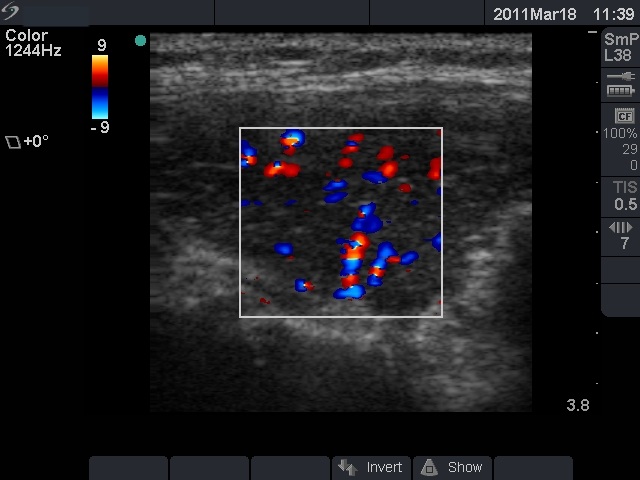

Ultrasonography: revealed hypoechogenic inhomogeneous thyroids with an echonormal circumscribed lesion in the left lobe corresponding to a secondary lobule.